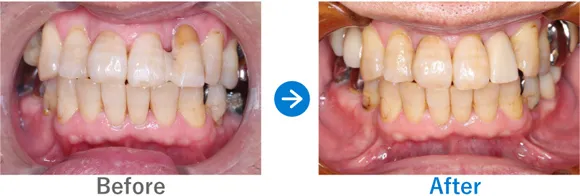

重度の歯周病で歯並びにも影響が。オールオン4で噛み合わせも改善

残存歯の動揺、義歯の不適合、重度の歯周病

上顎 オールオン4、下顎 オールオン4

7,150,000円(上顎3,575,000円、下顎3,575,000円/内訳:オールオン4(ストローマン)、3Dモデルガイド*、仮歯、セデーション、ボツリヌストキシン注射、3D模型、保証10年)

治療結果

もともと重度の歯周病があり、残っている歯が動いてしまい歯が前に出ているような並びになっていました。そのため、正常な位置で嚙み合わせるように設計し、オールオン4治療を行いました。歯周病に加え喫煙も続けているため、インプラント周囲炎にはとくに注意が必要です。